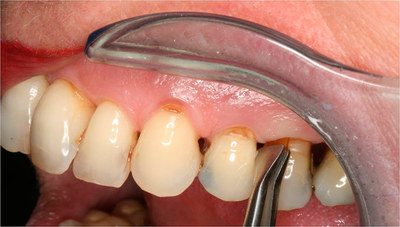

Визуальная диагностика

Периодонтит — коварное заболевание, подразделяющееся на разные виды и формы.

Специалисты отмечают общие признаки для всех стадий недуга: гнилостный запах изо рта, кровоточивость дёсен во время проведения гигиенических процедур, боль различной степени, ощущение выросшего зуба.

Определить периодонтит на ранних этапах заболевания сложно, но возможно, благодаря внимательной визуальной диагностике.